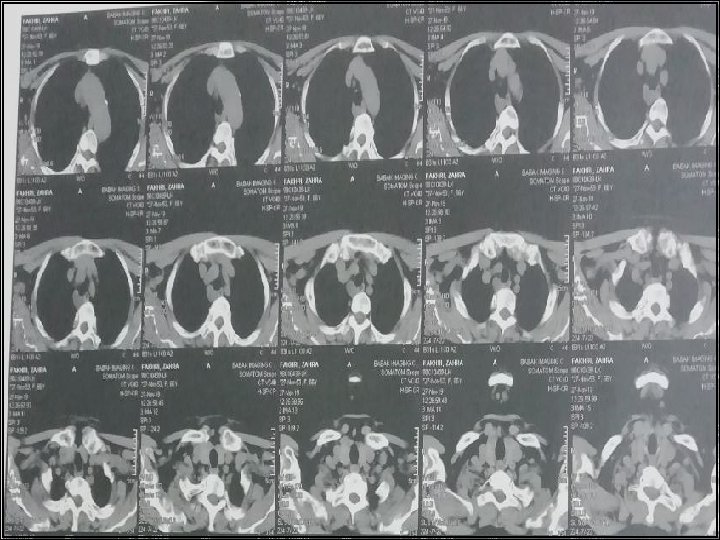

CT Scan axial of neck with and without IV Contrast 98/6/9

CT scan of chest with and without contrast 98/6/9